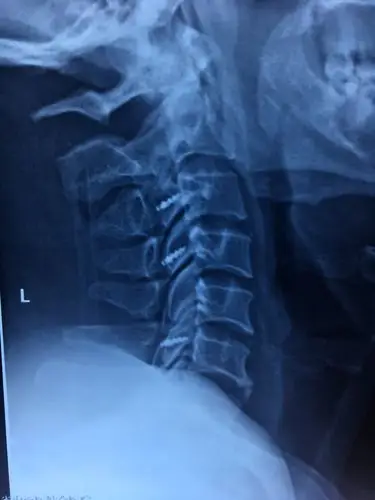

颈椎后纵韧带骨化症opll常见问题解答

术后颈椎四位片